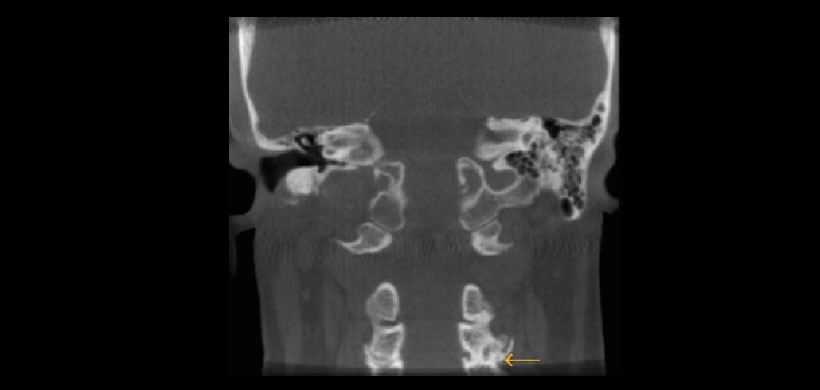

Fig 5. Tomografía volumétrica, vista coronal. Muestra cambios degenerativos (osteoartritis) a nivel de C3 y C4 con formación de osteofito.